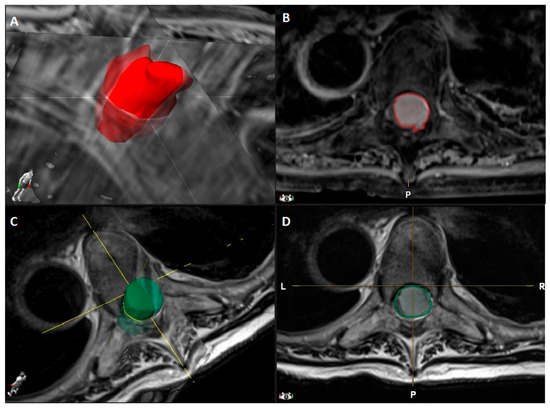

- Tumor volume (cm3) manually segmented using Brainlab Elements® on axial T1- weighted images with contrast (slice thickness from 3 to 4 mm) (Figure 1).

Figure 1. Dorsal Th5-Th6 WHO grade I meningioma with anterior dural attachment: (A) 3D tumor volume rendering (2.6 cm3) obtained by (B) tumor segmentation on axial T1-weighted MRI images after contrast administration using Brainlab Elements®; (C) Spinal canal volume rendering (3.5 cm3) obtained by (D) spinal canal segmentation on axial T2-weighted MRI images using Brainlab Elements®. - Canal volume (cm3) manually segmented using Brainlab Elements® on axial T2- weighted images (slice thickness from 3 to 4 mm) to assess the volume of the corresponding spinal canal segment (identified by the segment between two axial slices corresponding to the upper and lower limits of the meningioma) (Figure 1).

- Areas (mm2) related to tumor and cord occupancy at maximum compression level and the degree of spinal cord compression, applying the formula reported by Davies et al. [19] and illustrated in Table 1, with the other previous studies reporting SMs volume analysis. The results are reported as % according to the author. This was calculated using OsiriX Lite® software, based on axial T1-weighted images with contrast and axial T2-weighted images (Figure 2).

Figure 2. Dorsal Th7 WHO grade I meningioma with anterior dural attachment: (A) Tumor area (111 mm2) measured at maximal compression on axial T1-weighted images after contrast administration; (B) spinal canal area (210 mm2) measured at maximal compression on axial T2-weighted images; (C) spinal cord area (39 mm2) measured at maximal compression on axial T2-weighted images; (D) postoperative spinal cord area (42 mm2) measured at the level of preoperative maximal compression on axial T2-weighted images. The measurements were made using OsiriX Lite®. - The degree of postoperative cord expansion (%) at the level of preoperative maximum compression calculated as above based on axial T2-weighted images.